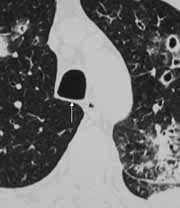

(radiol.) Una opacidad lineal orientada verticalmente, de una amplitud entre 2 y 5 mm., la cual se extiende desde la entrada torácica superior hasta la bifurcación de la tráquea y visible sólo en la radiografía lateral del tórax. Está situada entre la sombra aérea de la tráquea y el pulmón derecho y está formada por la pared traqueal posterior y tejido mediastinal adyacente. (figuras 3a y 3b).

| Figura 3a. Radiografía lateral de tórax: Banda traqueal posterior (flechas). | Figura 3b. TAC mostrando Banda traqueal posterior con pulmón derecho en el receso supraácigos. |